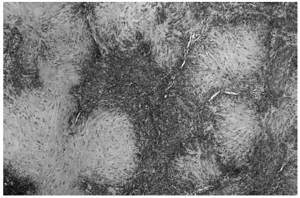

Las áreas hipocelulares presentaban un estroma escleroso. Las células que contenían se disponían en haces no muy bien estructurados. Estas células mostraban un núcleo alargado con extremos redondeados que recordaban fibras musculares lisas (fig. 4).

Fig. 4.--Detalle de una transición entre una zona hipocelular con células fusiformes dispuestas en haces no muy bien estructurados con un estroma hialinizado y una zona hipercelular.